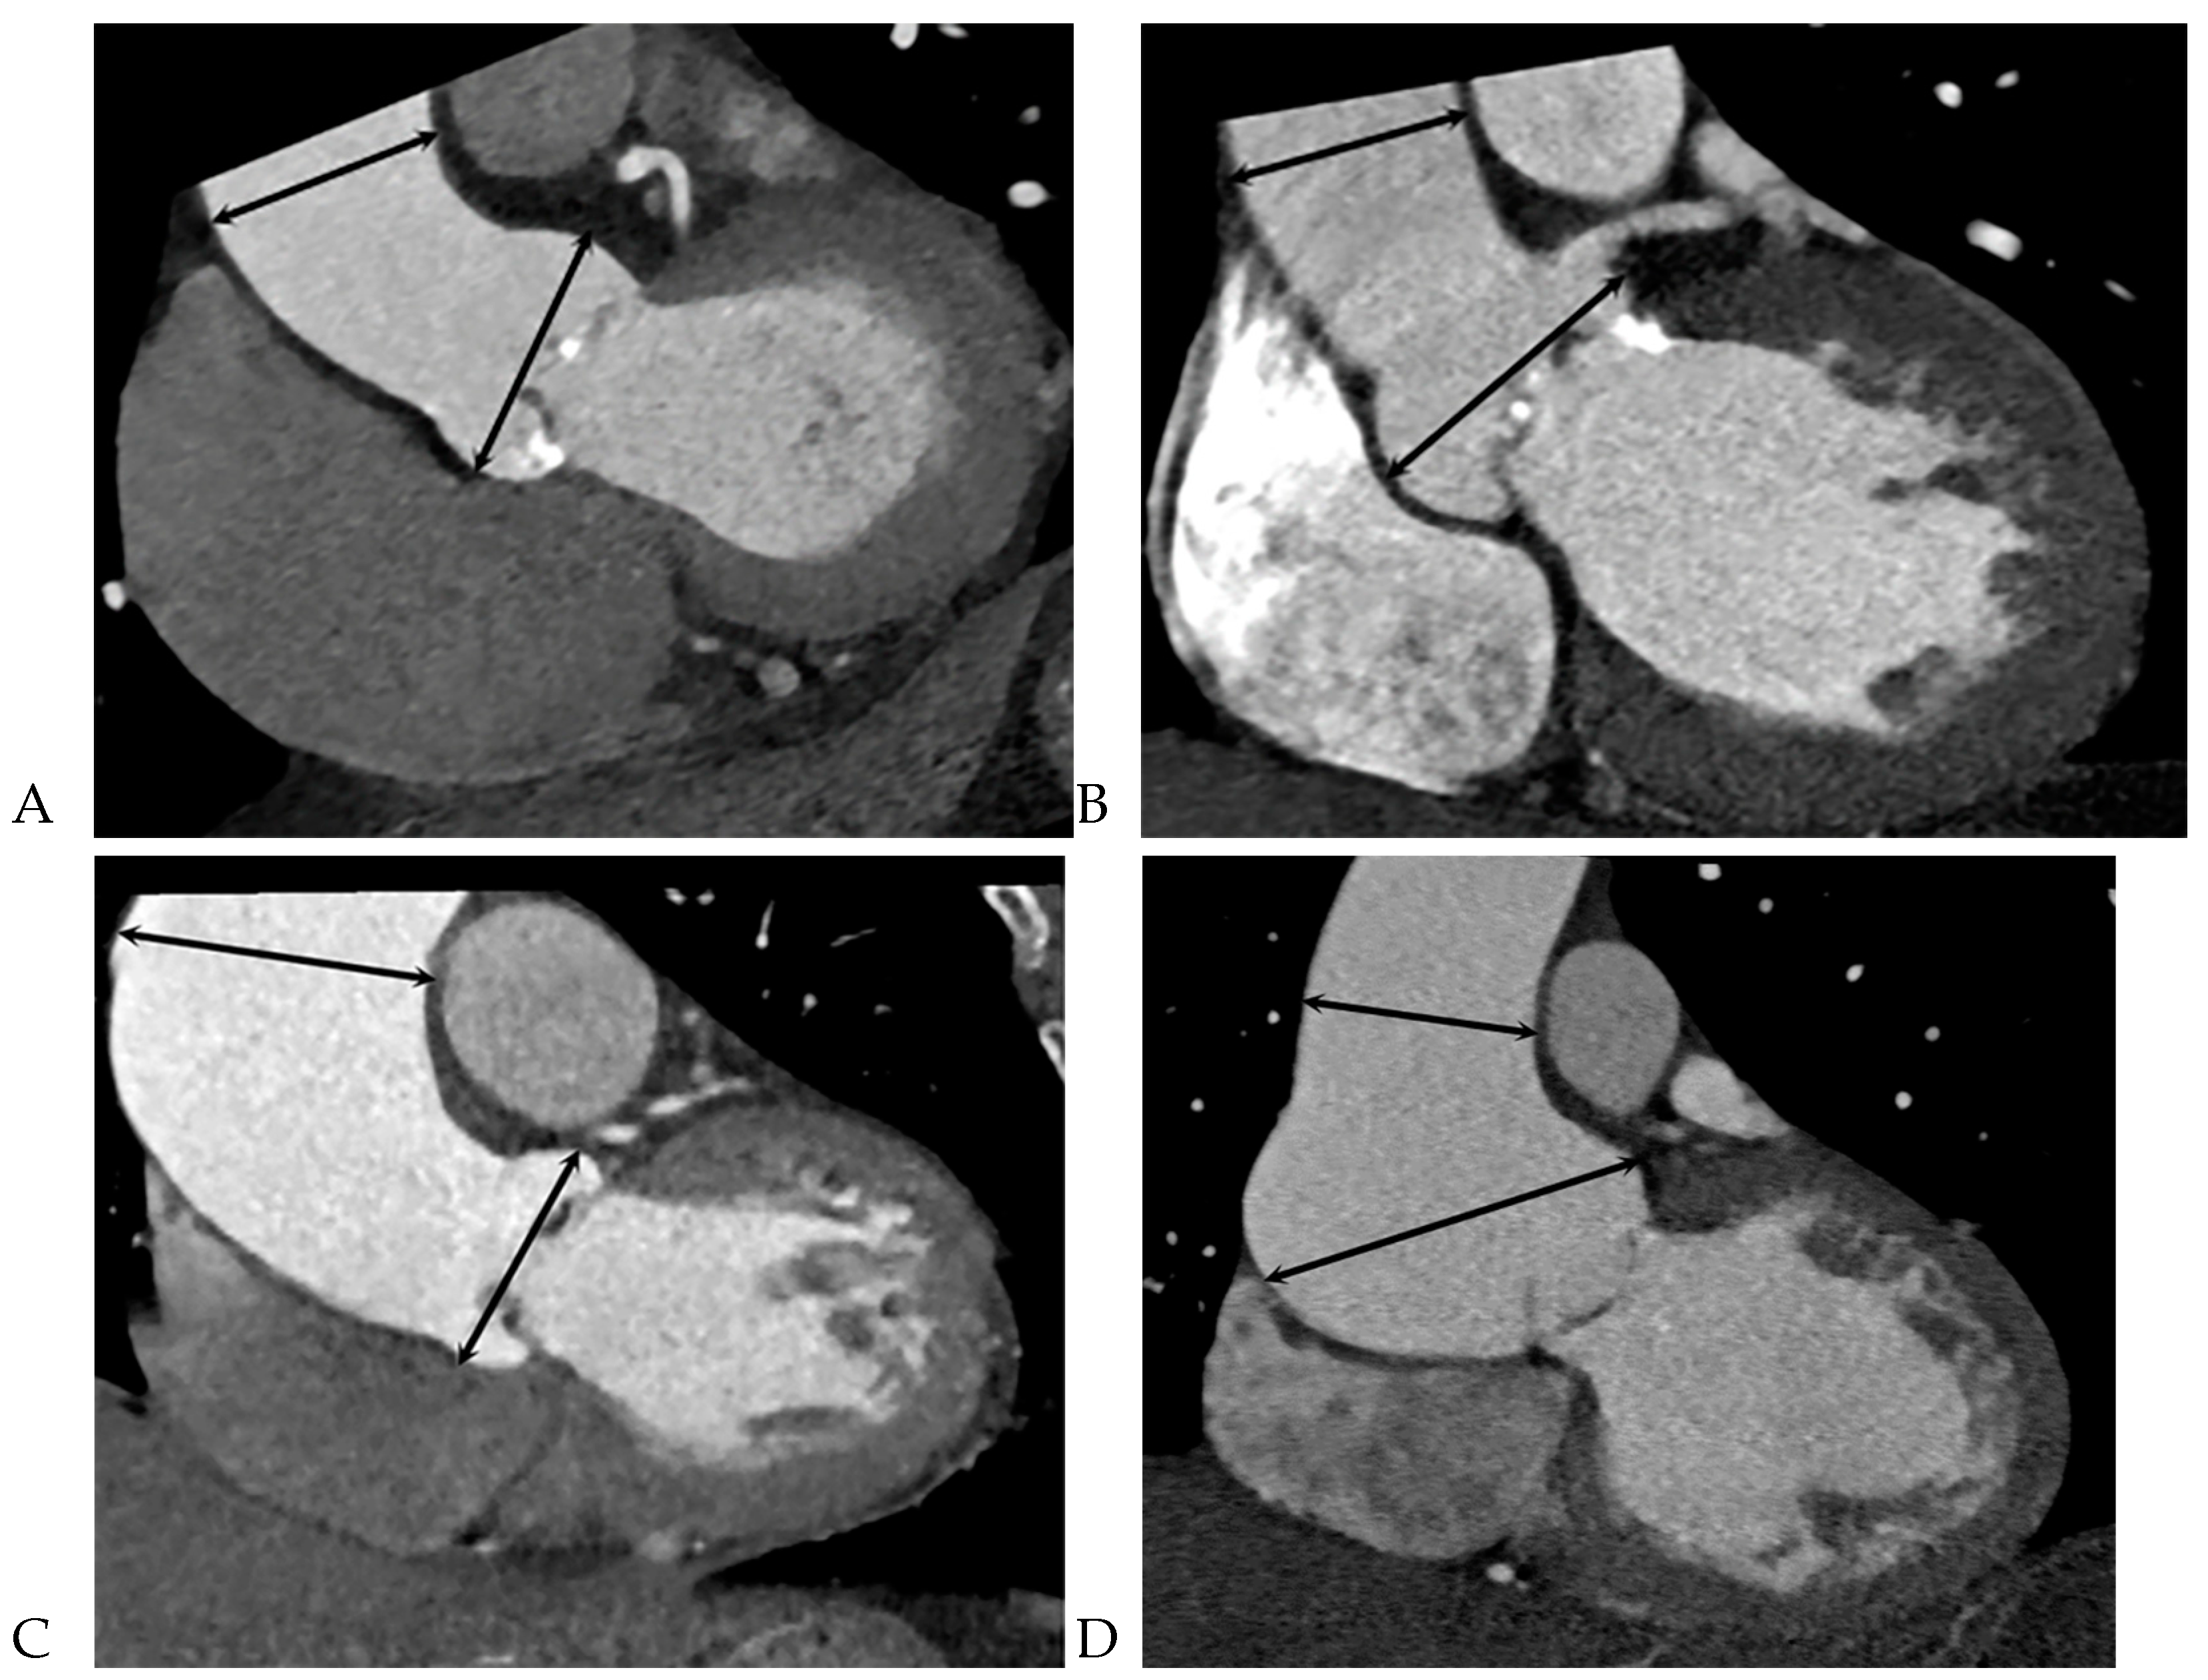

All CCT images were reviewed by a consensus of two radiologists with 16 and 5 years of experience, respectively, who were blinded to the clinical and surgical data. BAV was defined as the presence of two cusps and commissures in both systole and diastole. The following morphological variables were assessed: (1) presence or absence of raphe and (2) ascending aortic diameter. The term “raphe” defines the conjoined or “fused” area of two adjacent undeveloped leaflets that turn into a malformed commissure between both leaflets [9]. BAV morphology was classified as raphe+ or raphe- according to the presence or absence of raphe (Figure 1) [10]. The dimensions of the ascending aorta were measured at the sinus of Valsalva and tubular portion. Double-oblique coronal images of the ascending aorta were reconstructed at 10 % or 20 % of the cardiac cycle (early to mid-systole) to measure the tubular portion of the ascending aorta dimensions. The measurement of the maximum dimension of the aortic sinuses of Valsalva was performed using a double oblique transverse view of the aortic root at 10 % or 20 % of the cardiac cycle (Figure 2). Aortopathy refers to progressive dilatation of the ascending aorta and is defined as indexed maximal aortic diameter exceeding 21 mm/m2 of the body surface area (BSA) [11]. Ascending aortic dilation configurations were slightly modified from the Fazel classification, which was assigned to four types depending on whether the segment of the vessel was exclusively or predominantly involved in dilatation: normal aorta, type 1, isolated dilation of the ascending aorta root at the level of the sinus of Valsalva [12]; type 2, middle ascending dilatation at the level of the tubular ascending portion; and type 3, combined dilatation of the aortic root and mid-ascending aorta (Figure 3) [12]. Aortic aneurysms are defined as those with dimensions greater than 50 mm. The association between the presence of raphe and the risk of aortic valve dysfunction and aortopathy was also analyzed.

Figure 3. Diameters of the ascending aorta measured with cardiac computed tomography at two different levels (sinus of Valsalva and tubular portion) at mid-to-end systole. The ascending aorta was assigned to one of four main anatomical types according to the segment of vessel exclusively or predominantly involved by dilatation based on the indexed maximal aorta diameter of exceeding 21 mm/m2 of body surface area: (A) normal. (B) type 1, root dilatation. (C) type 2, ascending aorta dilatation. (D) type 3, combined dilatation of aortic root and middle ascending aorta.